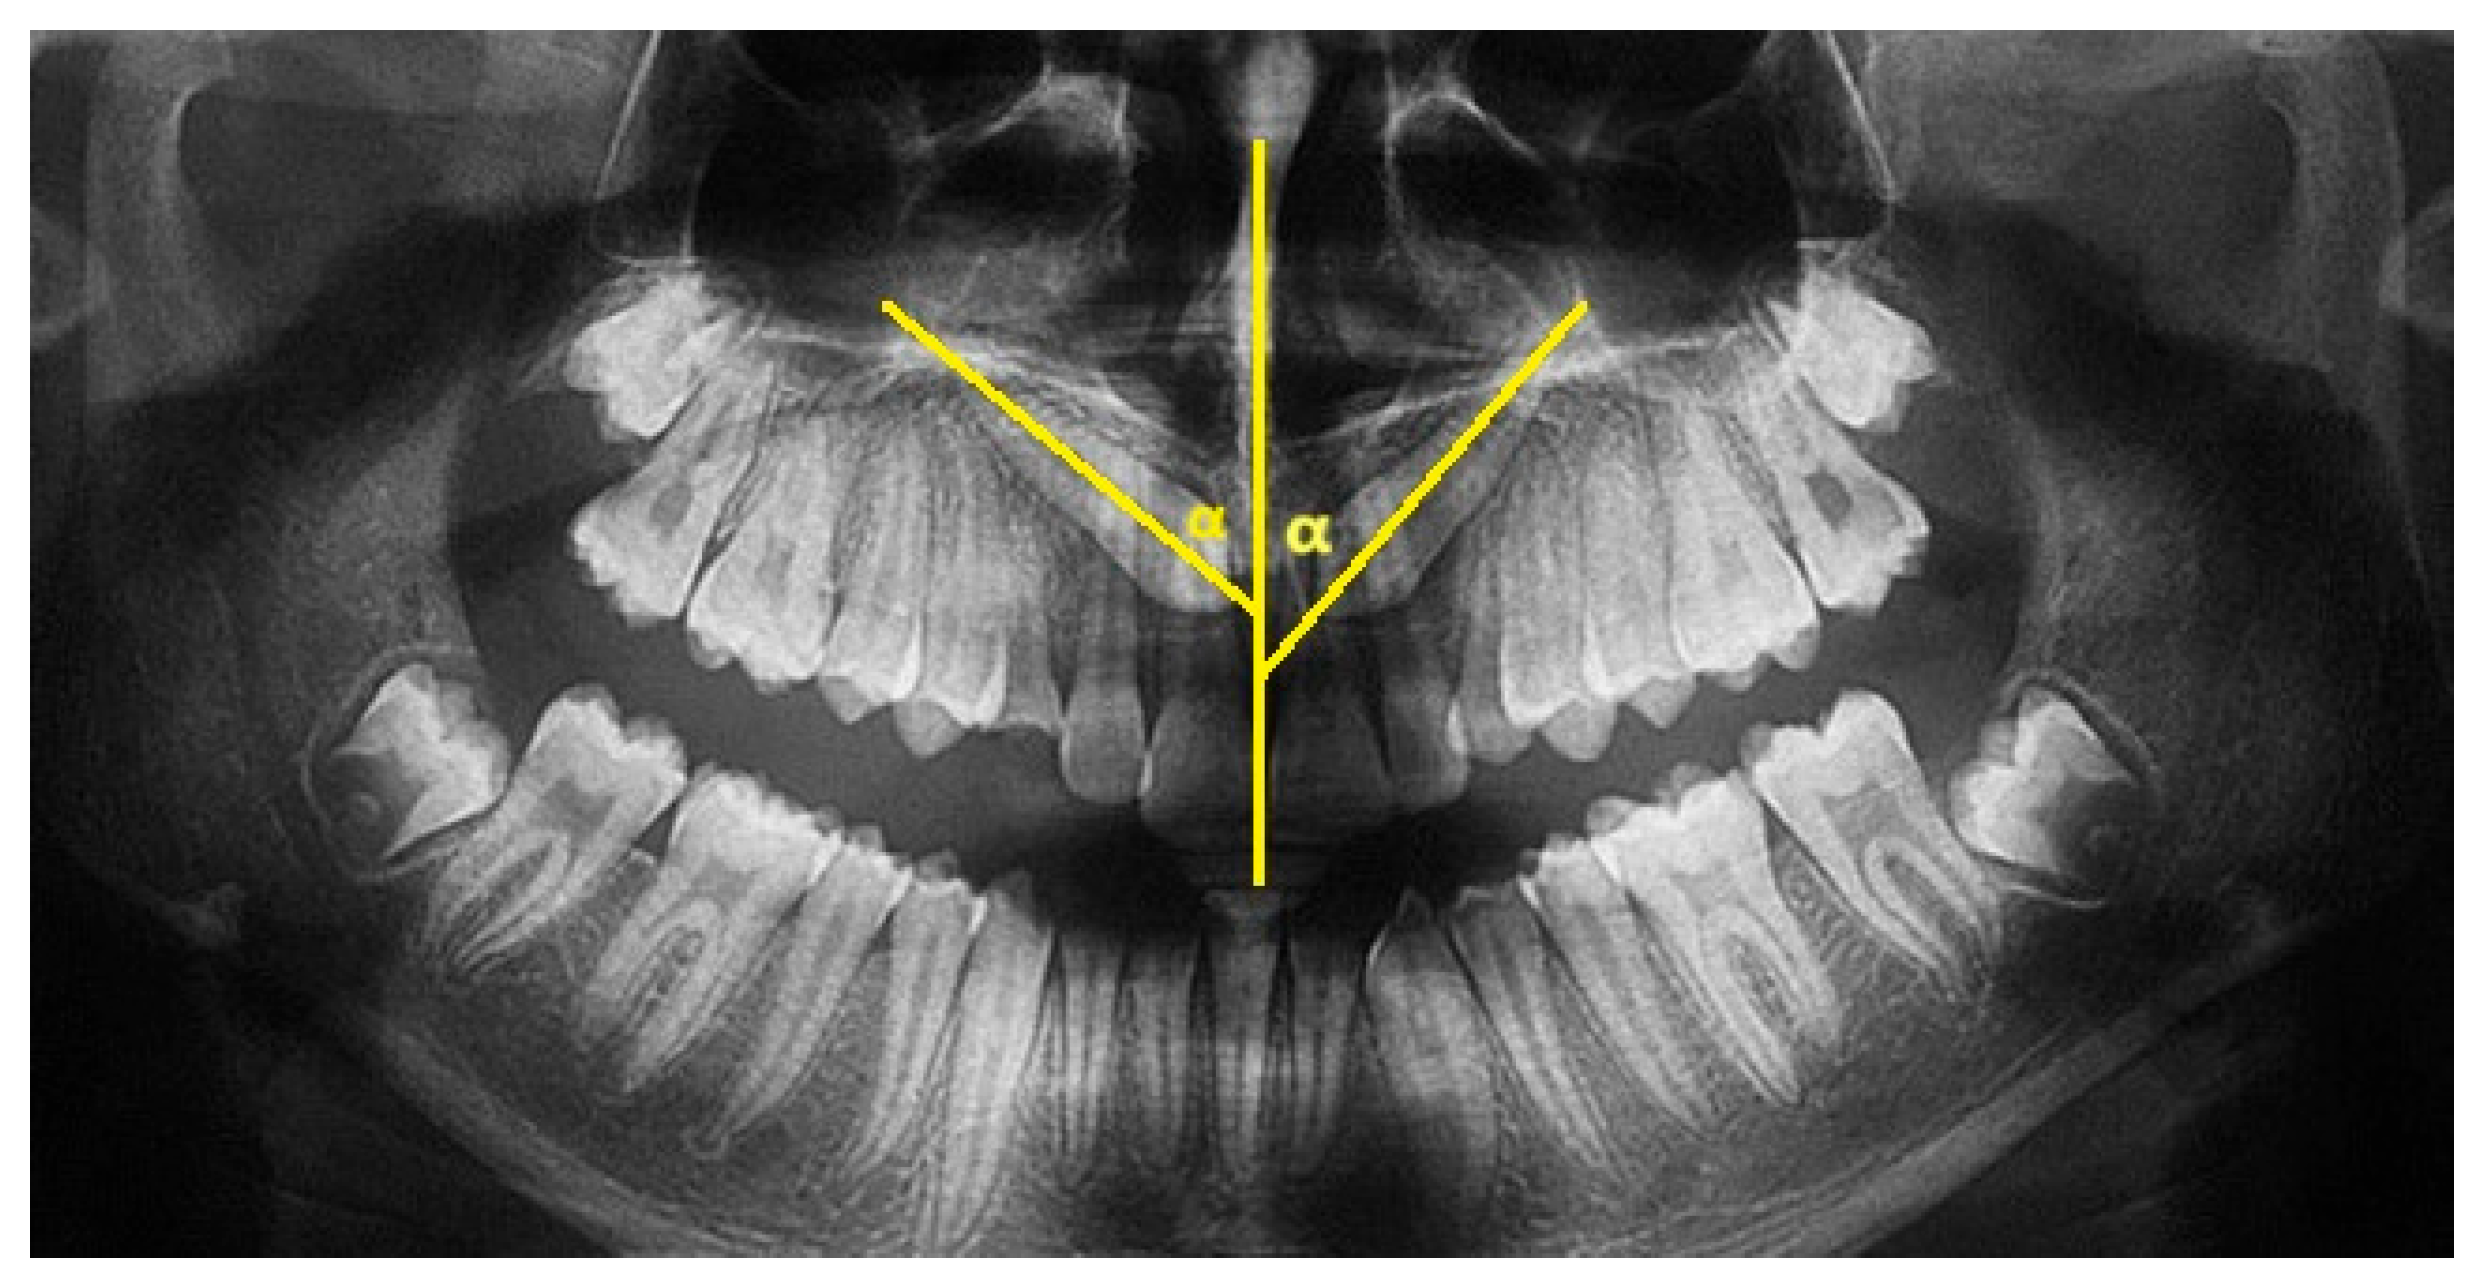

The height of inclusion was measured on CBCT. This new measurement was introduced as it is considered to be easy to perform. The software ‘3D Slicer’ (an open-source platform for visualization and analysis of three-dimensional medical images, including DICOM files of CBCTs) was used to evaluate the inclusion height of the maxillary canine relative to the occlusal plane. 3D Slicer software (version 5.6.1) was also used to export the CBCT, performed before surgery, into STL files. The DICOMs were imported into the software; the areas of interest (upper arch) were cropped using the ‘Crop Volume’ function; then the structures of interest, i.e., the upper dental elements, were segmented using the ‘Segment Editor’ function; and finally, the STL files were exported.

This measurement was performed by tracing the occlusal plane for each patient, using the mesio-palatal cusps of the upper first molars and the incisal edge of the upper central incisors at the interincisal midline as three reference points. A line perpendicular to the newly created occlusal plane was then drawn from the cusp of the maxillary canine included to the occlusal plane, thus obtaining the millimeter value of canine inclusion height (Figure 3).

Figure 3.

Inclusion height measured on CBCT (Green circle: occlusal plane; Red circle: Cusp or the maxillary canine included; L_2: distance between the cusp of the impacted canine and the occlusal plane; P_9: Posterior reference for occlusal plane.).